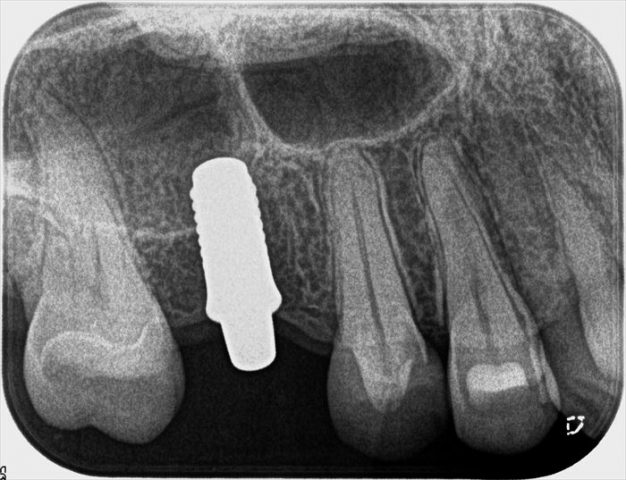

埋入オペ後のデンタルレントゲン写真です。

安堵する瞬間です。

アバットメントまでがワンピース構造になっているティッシュレベルインプラントです。

インプラントの骨結合の治癒を待って、この突起の部分にかぶせもの(セラミッククラウン)をセットします。

上下顎の咬合位の確認です。

アバットメントが突出した状態になりますので、適切な埋入トルクで埋入できることが重要です。

上下のクリアランスも適切でなければなりませんし、埋入位置がすべてです。